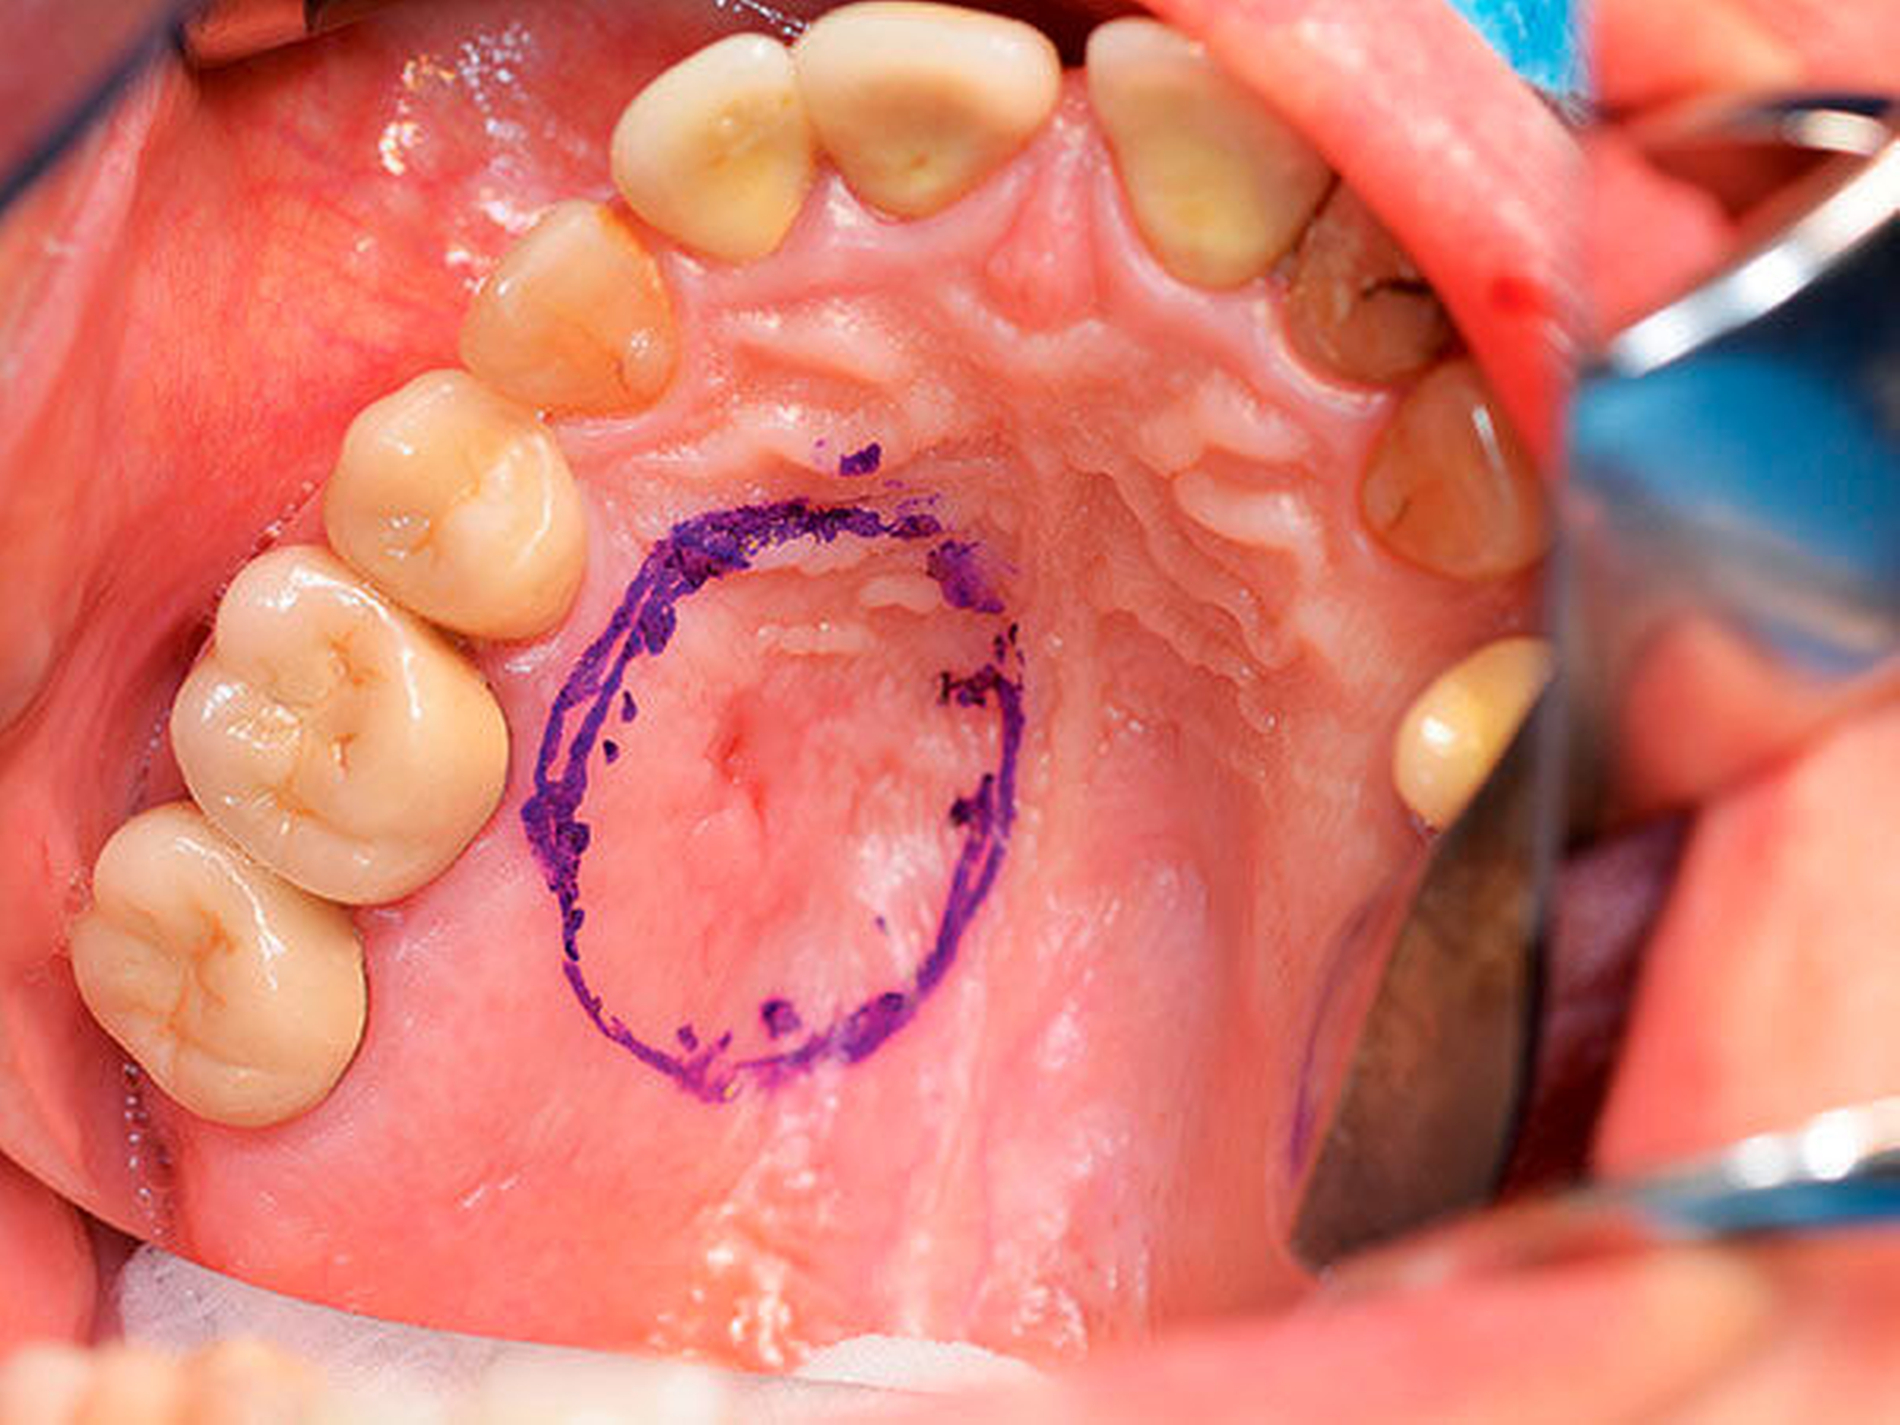

Mit einem histopathologisch alio loco gesicherten Low-grade-Adenokarzinom der kleinen Speicheldrüsen des linken Hartgaumens, das nach konsiliarpathologischer Mitbeurteilung als sekretorisches Karzinom eingestuft wurde, stellte sich eine 51 Jahre alte Frau in der Klinik für Mund-, Kiefer- und Gesichtschirurgie der Universitätsmedizin Mainz, vor. Bei Aufnahme imponierte eine 0,5 cm große Induration des linken Hartgaumens Regio 24/25 bei Zustand nach Probenentnahme alio loco (Abbildung 1).

Nach ausführlicher Aufklärung über den Eingriff, Risiken, mögliche Komplikationen, Behandlungsalternativen und die Folgetherapie erfolgte die Operation in Intubationsnarkose (Abbildung 2). Nach der Tumorresektion wurde die Nachresektion des Hartgaumens zur Tiefe mittels Abtragung des kortikalen Knochens durchgeführt. Zur Infektions- und Blutungsprophylaxe wurde postoperativ eine präoperativ angefertigte Verbandplatte eingegliedert.